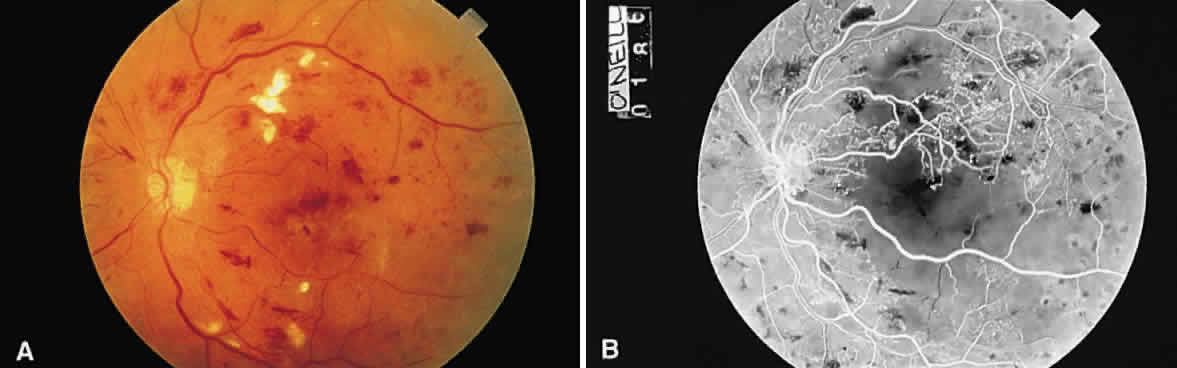

Microaneurysms, such as those seen in diabetic retinopathy (Fig. 52), are reflective of vascular abnormality, which has been demonstrated histologically using trypsin-digestion techniques (Fig. 53). Notice that many microaneurysms measure less than 60 μm in diameter. Since the maximum resolving power of the direct ophthalmoscope is 60 μm, many of the small red dots observed in the fundus are not microaneurysms but microhemorrhages. In fact, alterations in vascular permeability are seen early in background diabetic retinopathy, and the microaneurysms frequently leak fluorescein during angiographic studies. Therefore, fluorescein angiography may be a more sensitive technique for the detection of microaneurysms than is direct fundus observation.18

Fig. 52. A. Fundus photograph of nonproliferative diabetic retinopathy. Notice the dilated veins, the small exudate clusters, the ischemic infarct (cotton-wool spot), and the numerous microaneurysms and small hemorrhages. B. Mid-venous phase fluorescein angiogram of the same eye. Notice the focal area of nonperfusion in the superior temporal arcade (ischemic areas), the fluorescing microaneurysms, and the hemorrhages, which appear dark in contrast to the background fluorescence. (Courtesy of William Tasman, MD, Philadelphia, PA)